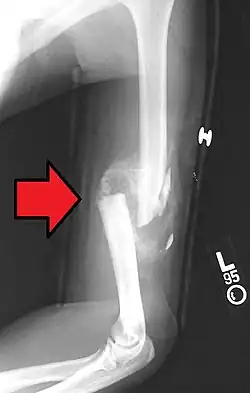

Вначале образуется соединительнотканная провизорная мозоль, к концу первой недели образуется остеоидная ткань, которая превращается либо непосредственно в костную, либо сначала в хрящевую, а затем в костную. Мозоль возникает из костеобразующих клеток надкостницы и эндоста. Образование костной мозоли играет важную роль в процессе срастания поврежденной кости. Костная мозоль, представляющая на рентгенограмме слегка затемненную область, в конце концов кальцифицируется и моделируется.

Костная мозоль перестраивается в нормальную кость примерно за один год.